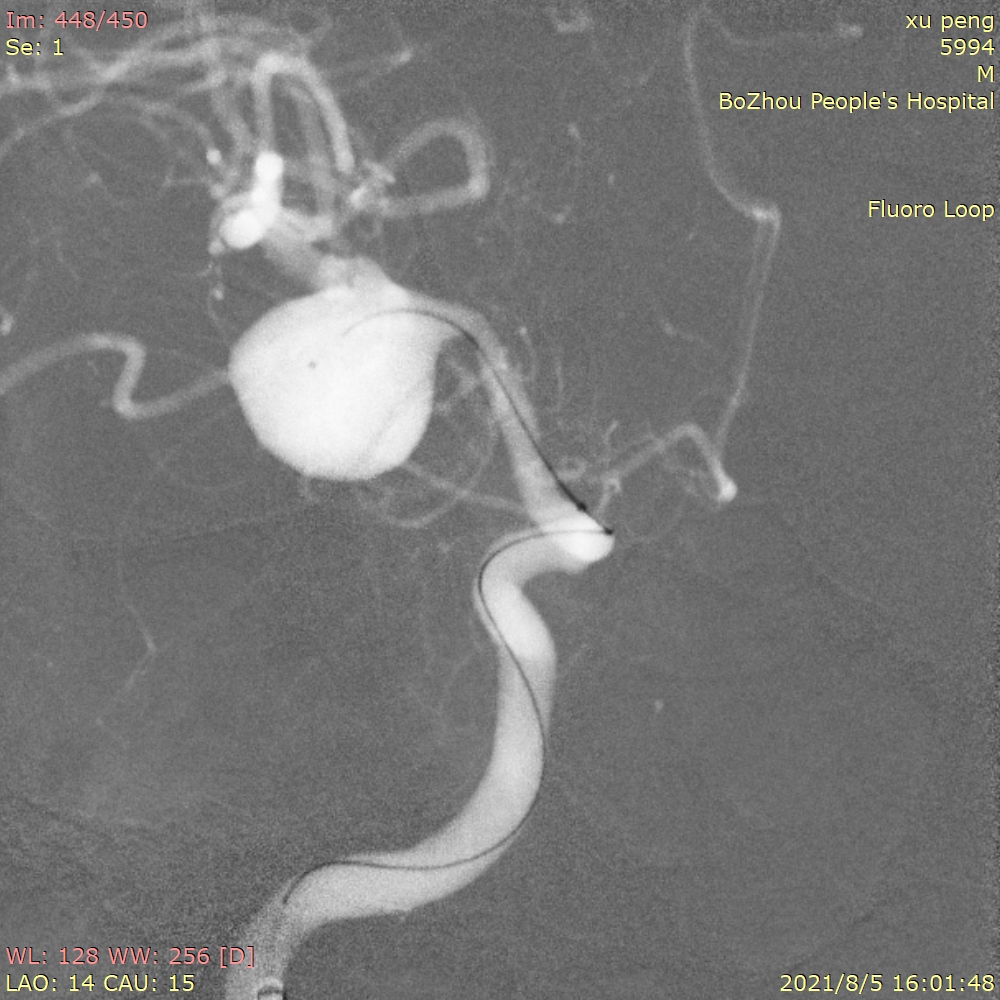

5、急诊查CTA提示:右侧大脑中动脉M1段巨大动脉瘤,和患者家人沟通后送导管室急诊造影。

右侧颈内动脉正位造影

右侧颈内动脉侧位造影

三维重建提示:右侧大脑中动脉M1段巨大动脉瘤,15.4mm*13.3mm大小,瘤颈7.1mm,近似球形,瘤顶指向下方。

工作位造影

先将第一根SL-10微导管塑形成“猪尾”后,顺利送入动脉瘤体内中心位置。我们打算先用一根微导管进行填圈,如果填圈顺利就不使用双导管技术。

选用Target 15/30作为成篮圈,经过小心、缓慢推送弹簧圈,使第一个圈的成篮形态和位置非常完美,弹簧圈瘤内完美贴壁,也基本覆盖瘤颈。

成篮圈的即刻造影和蒙片